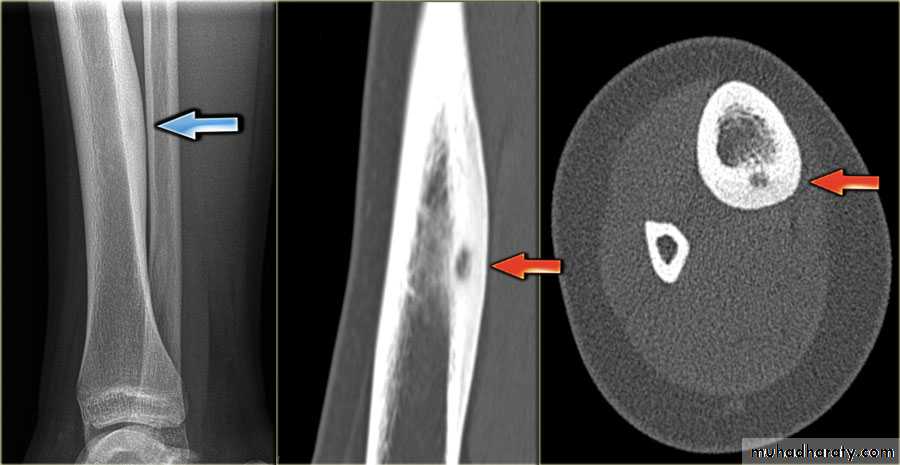

IV. computed tomography in bone disease (CT scan ) :

1.Demonestrating abnormality in the pelvis and spine2.Demonstrating the extent & characterization of bone tumour in selected cases to complement MRI

3.As gide of bone biopsy

the initial radiological decision is usually to try &decide whether the solitary lesion is benign or its aggressive by looking for the following features on plain radiographs & CT :

1.Zone of transition

2.The adjacent cortex

3.Expansion

4.Periosteal reaction

5. Calcific densities within the lesion

Enchondromas :Fibrous cortical defects ( non ossifying fibromas )